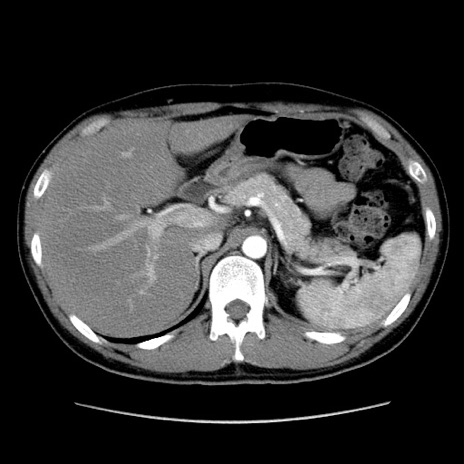

症例36(横断像)

【症例】20歳代 男性

【主訴】心窩部痛

【現病歴】今朝より上腹部痛あり。一旦軽快していたが再度出現したため救急要請。昨日夕に白身の魚を含む刺身を食べた。

【身体所見】BP 136/89mmHg、HR 74/min、BT 37.0℃、腹部:膨満、軟、心窩部に圧痛あり。反跳痛なし、筋性防御なし、腸雑音やや亢進あり。

【データ】WBC 17700、CRP 0.48